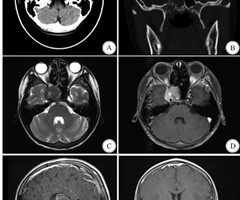

造影剂脑病1例报道并文献复习

【摘要】目的分析1例数字化减影血管造影(DSA)中使用碘克沙醇造影剂导致造影剂脑病(CIE)的全病程。方法回顾性分析南京鼓楼医院江北院区2023年12月收治的1例DSA术中使用碘克沙醇造影剂后导致CIE 患者的临床资料。结果本例患者在术后出...